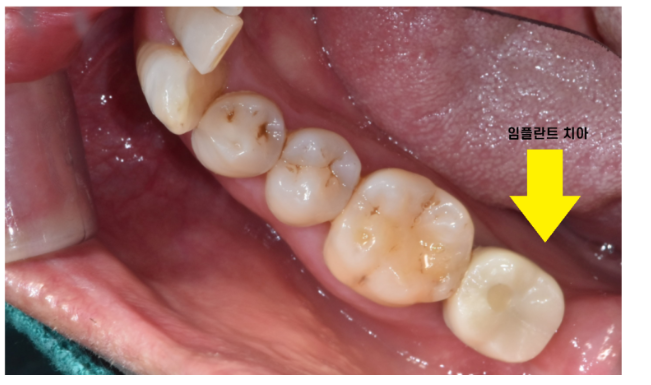

240307

임플란트 보철의 특성상

처음에는 임시로 약하게 붙여드렸습니다.

테스트 하는 기간을 거쳐보는거죠~

오랫동안 치아가 없다보니 볼을 씹는다거나

불편감이 생길 수 있기에..

불편하시면

수정이 들어가야하니까요~

디지털 방식으로 제작하여 예측했던 그대로

역시나 큰 불편감 없이 치료가 마무리되었습니다.